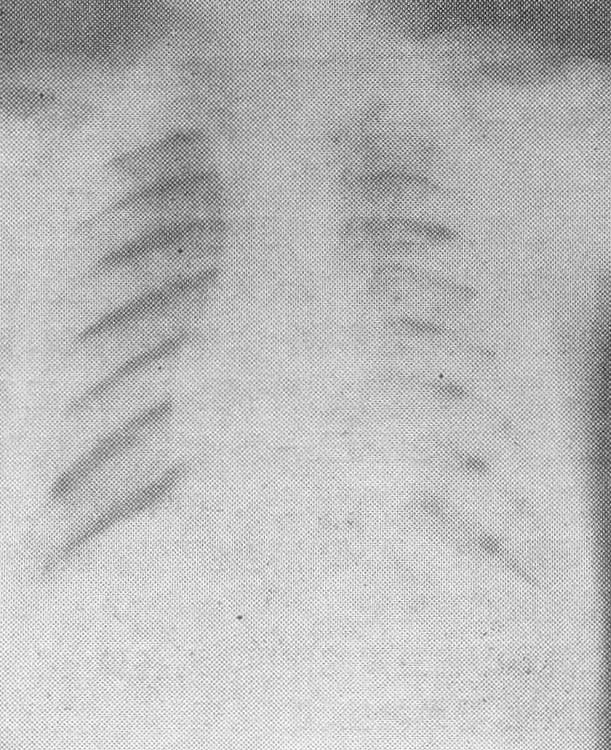

图2 氟骨症胸部X线片肋骨骨质明显致密硬化,肌肉韧带附着处有钙化